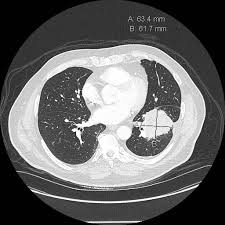

In radiology, a solitary pulmonary nodule (SPN) or coin lesion is a mass in the lungsmaller than 3 centimeters in diameter. It can be an incidental finding found in up to 0.2% of chest X-rays and around 1% of CT scans. The nodule most commonly represents a benign tumor such as a granuloma orhamartoma, but in around 20% of cases it represents a malignant cancer, especially inolder adults and smokers. Conversely, 10 to 20% of patients with lung cancer are diagnosed in this way. Thus, the possibility of cancer needs to be excluded through further radiological studies and interventions, possibly including surgical resection. Theprognosis depends on the underlying condition. A solitary pulmonary nodulus needs to be separated from larger lung tumors, smaller infiltrates or masses with other accompanying characteristics. An often used formal radiological definition is the following: a single lesion in the lung completely surrounded by lung parenchyma (functional tissue) with a diameter less than 3 cm and without associatedpneumonia, atelectasis (lung collapse) or lymphadenopathies (swollen lymph nodes). ot every round spot on a radiological image is a coin lesion: it should not be confused with the projection of a structure of the chest wall or skin, such as a nipple, a healing rib fracture or electrocardiographic monitoring.

The most important cause to exclude is a form of lung cancer, including rare forms such as primary pulmonary lymphoma, carcinoid tumor and a solitary metastasis to the lung (common unrecognised primary tumor sites are melanomas, sarcomas or testicular cancer). Benign tumors in the lung include hamartomas and chondromas. The most common benign coin lesion is a granuloma (inflammatory nodule), for example due to tuberculosis or a fungal infection. Other infectious causes include a pulmonary abscess, pneumonia (including Pneumocystis carinii pneumonia) or rarely nocardial infection or worm infection (such as dirofilariasis or dog heartworm infestation). Lung nodules can also occur in immune disorders, such asrheumatoid arthritis or Wegener's granulomatosis, or organizing pneumonia.

An SPN can be found to be an arteriovenous malformation, a hematoma or an infarction zone. It may also be caused by bronchial atresia, sequestration, an inhaled foreign body or pleural plaque. Several features help to distinguish benign conditions from possible lung cancer. The first parameter is the size of the lesion: the smaller, the less risk for malignant cancer. Benign causes tend to have a well defined border, whereas lobulated lesions or those with an irregular margin extending into the neighbouring tissue tend to be malignant.  If there is a central cavity, then a thin wall points to a benign cause whereas a thick wall is associated with malignancy (especially 4mm or less versus 16mm or more). In lung cancer, cavitation can represent central tumor necrosis (tissue death) or secondary abscessformation. If the walls of an airway are visible (air onchogram), bronchioloalveolar carcinomais a possibility. An SPN often contains calcifications. Certain patterns of calcification are reassuring, such as the popcorn-like appearance of hamartoma. An SPN with a density below 15 Hounsfield units on computed tomography tends to be benign, whereas malignant tumors often measure more than 20 Hounsfield units. Fatty tissue inside hamartomas will have a strongly negative value on the Hounsfield scale. The growth velocity of a lesion is also informative: very fast or very slow growing tumors are rarely malignant, in contrary to inflammatory or congenital conditions. It is therefore important to retrieve previous imaging studies to see if a lesion was presented and how fast its volume is increasing. This is more difficult for nodules smaller than 1 centimeter. Moreover, the predictive value of stable lesion over a period of 2 years has been found to be rather low and unreliable. The work-up in patients with a solitary pulmonary nodule is based on an initial risk assessment. If the risk of malignancy is thought to be low, follow-up imaging (usually serial CT scans) can be planned at a later time. The frequency of further scans can be determined by the patient's risk for cancer and the size of the nodule. If the initial impression is that there is a high likelihood of cancer, then a surgical intervention is appropriate (provided that the patient is fit for surgery). If there is an intermediate risk of malignancy, further imaging with positron emission tomography (PET scan) is appropriate (if available). Around 95% of patients with a malignant nodule will have an abnormal PET scan, while around 78% of patients with a benign nodule will look normal on PET (this is the test sensitivity and specificity). Thus, an abnormal PET scan will reliably pick up cancer, but several other types of nodules (inflammatory or infectious, for example) will also show up on a PET scan. If the nodule has a diameter below 1 centimeter, PET scans are often avoided because there is an increased risk of falsely normal results. Cancerous lesions usually have a high metabolism on PET, as demonstrated by their high uptake of FDG (a radioactive sugar). If the lesion is found on further imaging to be suspicious, it should be surgically excised (via thoracotomy or video-assisted thoracic surgery) to confirm the diagnosis by microscopical examination.